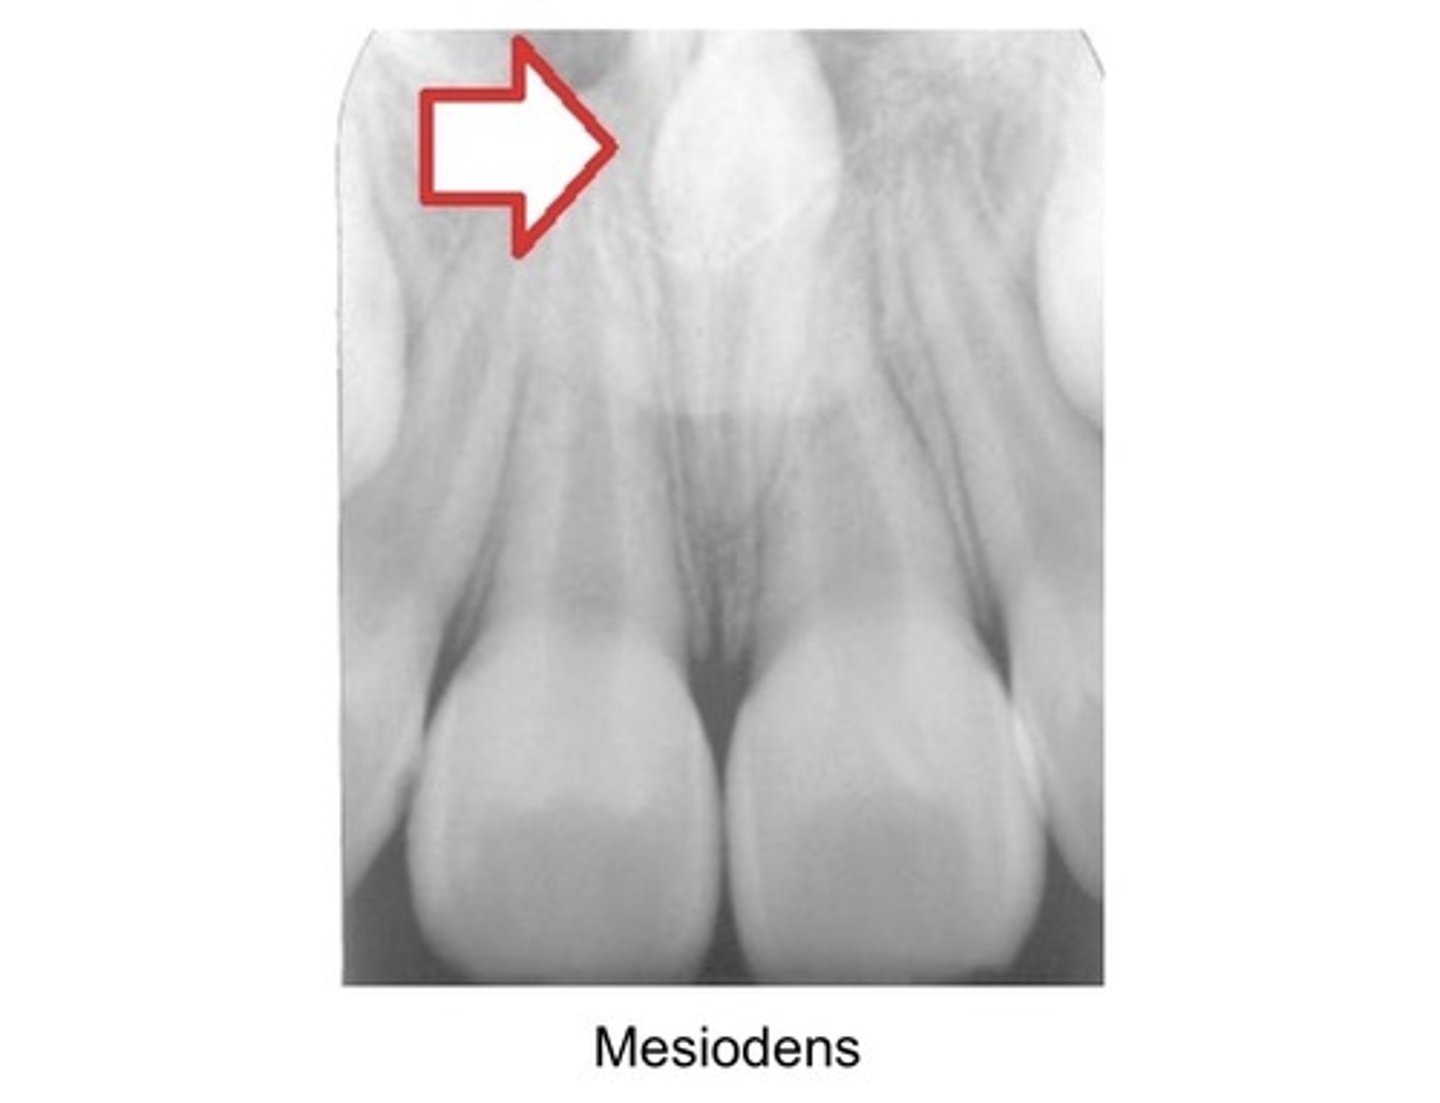

Most common single supernumerary tooth?

Mesiodens

Location of Mesiodens?

Btwn maxillary centrals